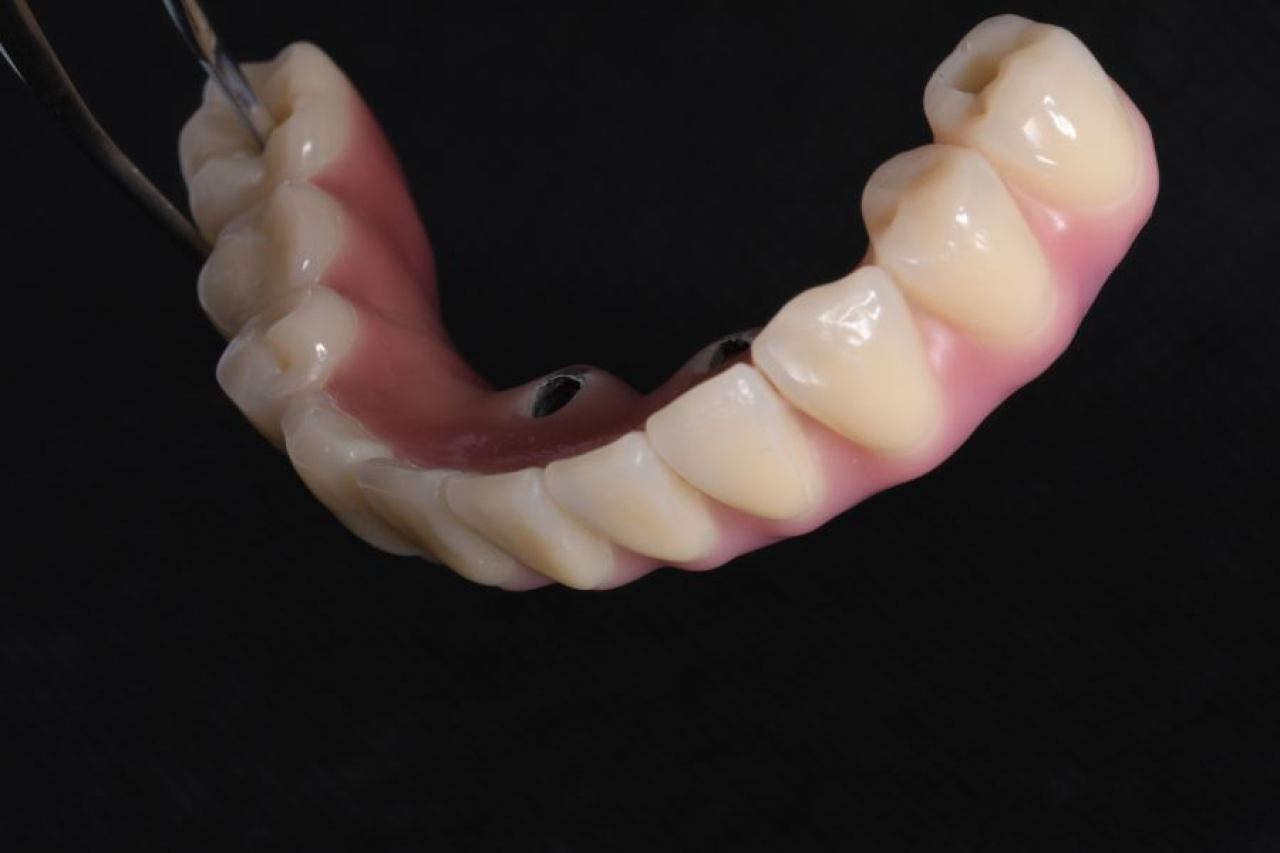

Implantologija - ugradnja dentalnih implantata

Dentalna implantologija je grana dentalne medicine koja objedinjuje znanje iz kirurgije, parodontologije i protetike i bavi se ugradnjom implantata u bezubu kost gornje ili donje čeljusti.

Marković Dental Clinic koristi najstariji, najistraživaniji i najkvalitetniji sustav dentalnih implantata Švedskog proizvođača Nobel Biocare.

All On 4 i All On 6 fiksni mostovi na 4-6 implantata, omogućavaju da se brzo, ekonomično i efikasno pacijentu od bezube čeljusti omogući mastikatorna i estetska funkcija.